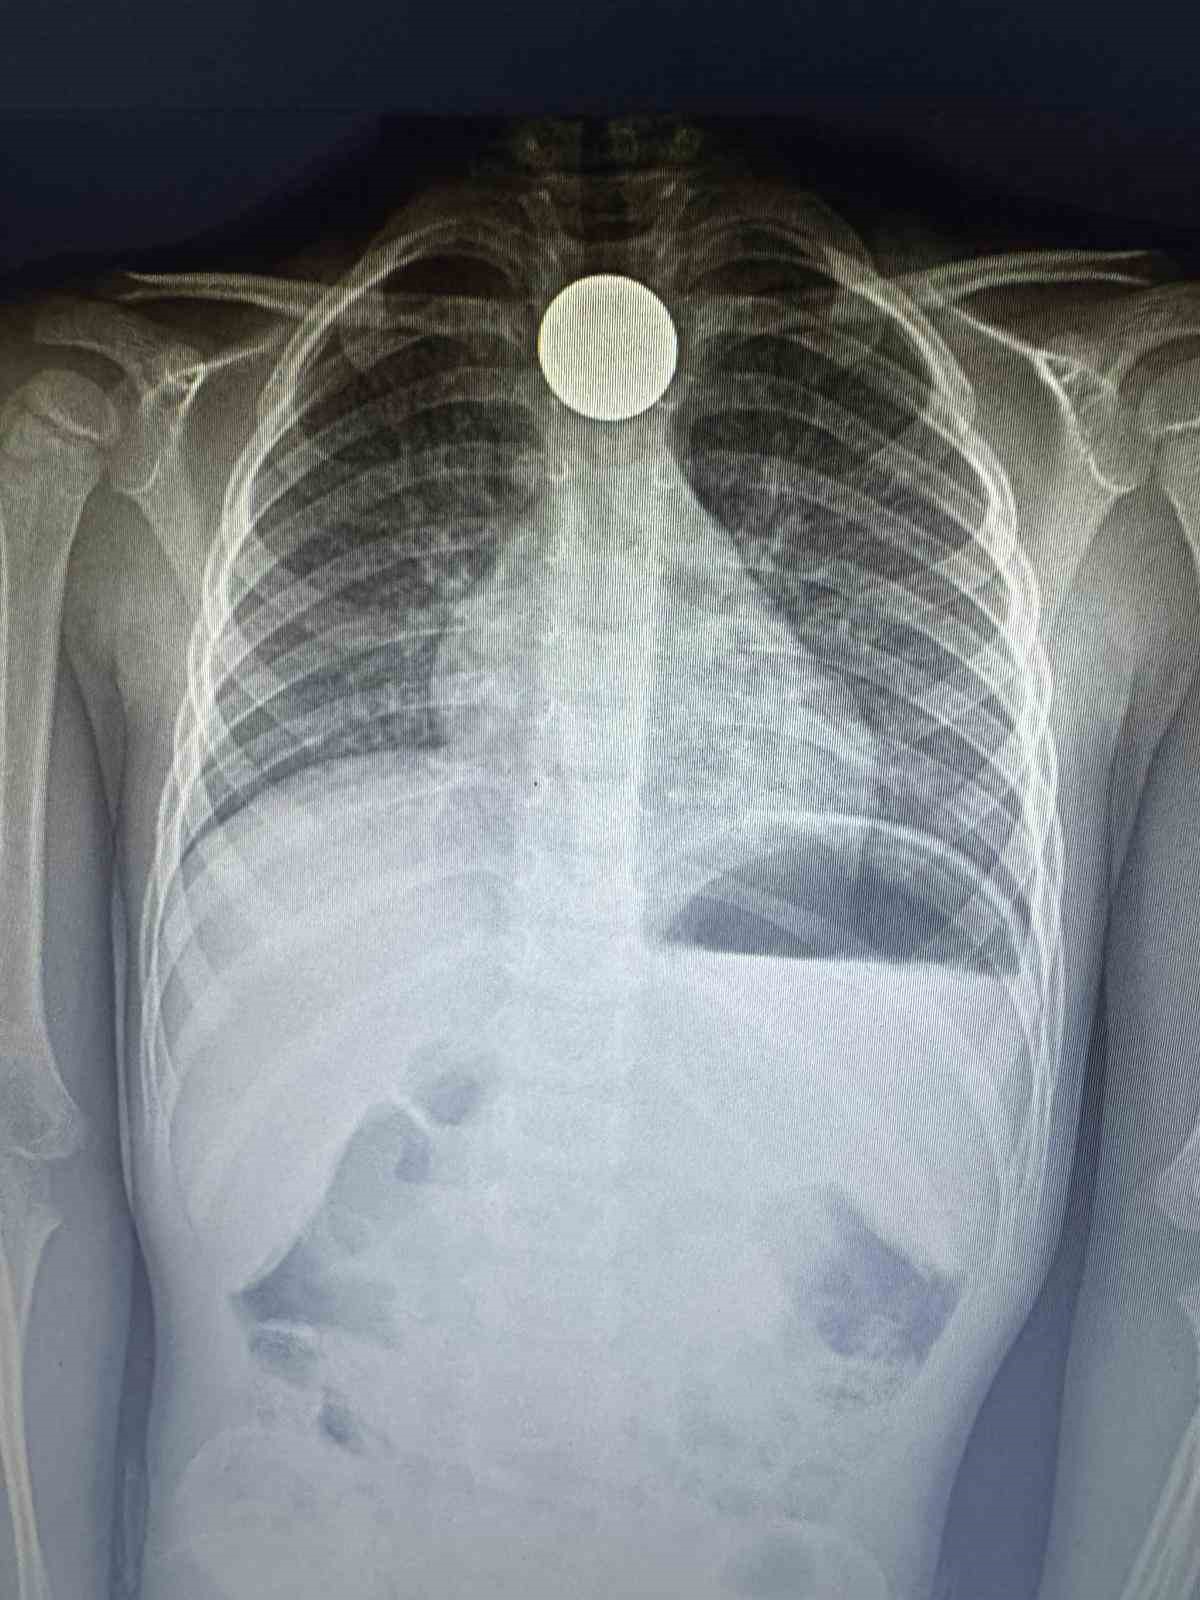

Dik durması hayatını kurtardı

Çekilen röntgende paranın boğazda dik olarak kaldığı görüldü. Doktorlar, paranın yan yatması durumunda küçük çocuğun nefes almasına engel olabileceği ve nefessiz kalarak hayati risk oluşturabileceği aileye anlatıldı. Yapılan 4 saatlik operasyonun ardından para boğazdan çıkarılırken, küçük çocuk ertesi gün taburcu edildi.

Yaşadıklarını anlatan baba Ziya Özden Tezgel, ikizleri Aras Hasan ve Ali’yi okuldan aldıktan sonra eve geldiklerini belirterek, “Çocukları aldığımda Aras Hasan ve Ali’nin okulda Kızılay Haftası ile ilgili etkinlik yaptıklarını öğrendik. Kızılay’a bağış yapmak için biriktirdikleri paraların bulunduğu kumbaralarını getirdiler. Salonda hep birlikte paraları sayıyorduk. Anneleri yemek yaptığı için kısa süreliğine içeriye geçtik. Kısa süre sonra Ali yanımıza geldi. Hasan’ın para yuttuğunu söyledi. Anne çıkarmaya çalıştı ancak olmadı. Antalya Eğitim ve Araştırma Hastanesi’ne götürdük. Çekilen ultrasonda paranın boğazda takılı olduğu görüldü. Doktorlar ameliyata alacaklarını söylediler. Çünkü para Aras Hasan’ın boğazındaki dik duruyordu. İyi ki öyle durmuş, böylece nefes alıp vermesine engel değildi. Doktorlar paranın yan durması halinde çocuğumuzu kaybedebileceğimizi söylediler. 4 saat ameliyatta kaldı. Genelde bu yaştaki çocuklar durumu pek idrak edemiyorlar. Sonrasında ise para ölüme kadar götürebiliyor” dedi.